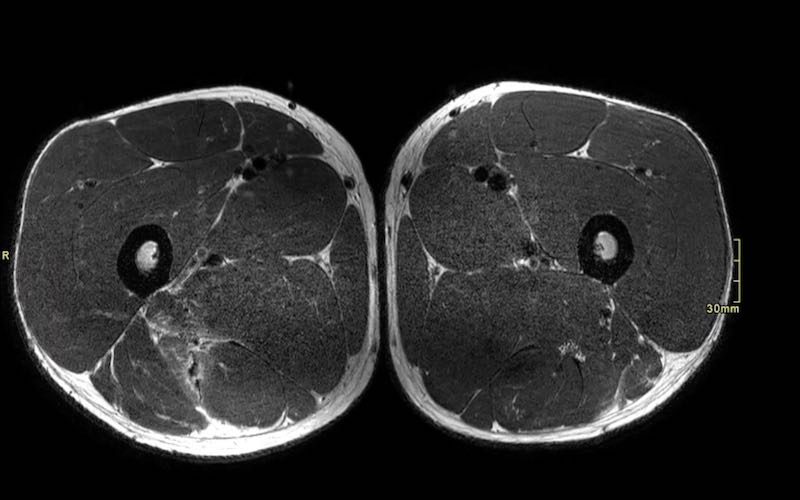

Trên các hình ảnh axial này, có thể thấy tăng tín hiệu và dày lên của gân cơ nhị đầu đùi bên trái (vòng tròn chấm vàng) khi so sánh với bên không bị tổn thương (vòng tròn chấm trắng).

Tại đây bạn có thể cuộn qua các hình ảnh axial. Có thể phóng to hình ảnh bằng cách nhấp vào chúng.

Đây là tổn thương bán phần, bắt đầu từ gân chung ở phía gần, bao gồm cả vùng MTJ và gân trong cơ ở phía xa hơn. Chiều dài vùng phù nề và mức độ biến dạng gân đều ở mức độ cao. Trường hợp này được phân loại là tổn thương BAMIC 3b/c.